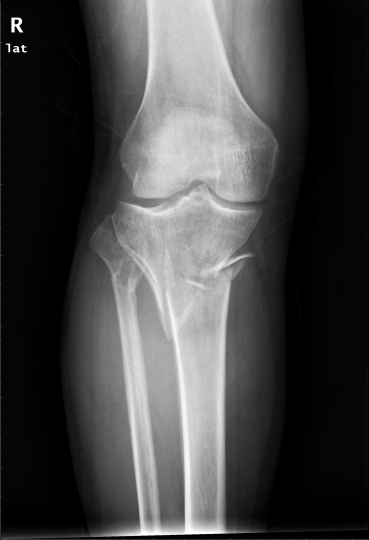

骨折是我们在日常生活中常见的一种疾病,通过手术治疗往往可以达到稳定的固定作用。手术固然重要,但术后功能康复亦不能忽视。小编最近就遇到一位胫骨平台骨折患者,该患者在4个月前发生了车祸导致胫骨平台骨折,并进行切开复位内固定手术治疗。但由于在术后一直畏痛少动,未进行积极地康复治疗,致使患侧膝关节难以像健侧一样伸直,下肢功能急剧下降。为了避免出现以上情况,今天小编就与您分享,胫骨平台骨折术后该如何正确康复。

胫骨平台是膝关节重要的负荷组成部分,也是膝关节创伤中最常见的骨折之一,多发生于强烈的外翻和内翻应力合并轴向载荷时,同时股骨髁对其下胫骨平台有压力和剪切力,可造成劈裂骨折、塌陷骨折或两者兼有。当发生胫骨平台骨折后,需要通过手术切开复位固定,术后要及时进行康复训练,以加快骨折愈合,促进患肢功能恢复。

1. 拍摄膝关节X光片复查,并根据骨折线愈合情况及专业医生建议决定是否开始进行患肢负重练习。